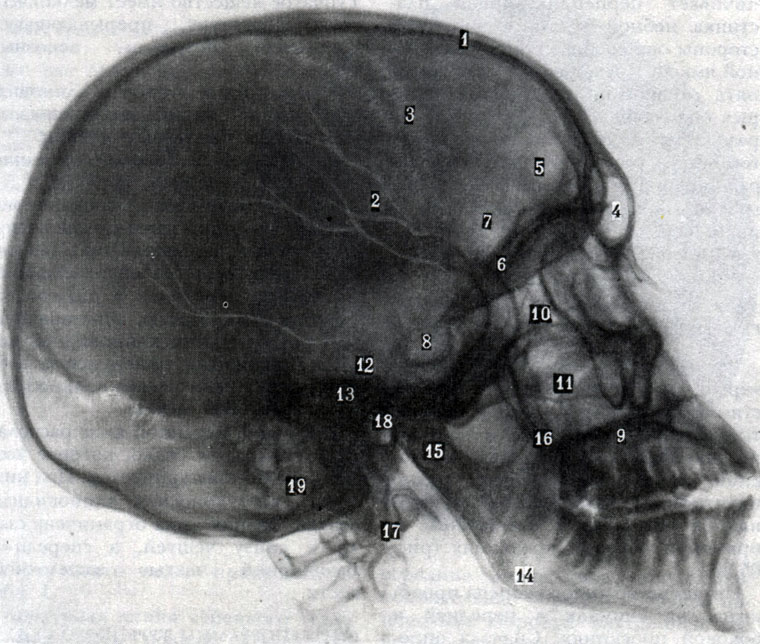

Анатомия сосцевидного отростка